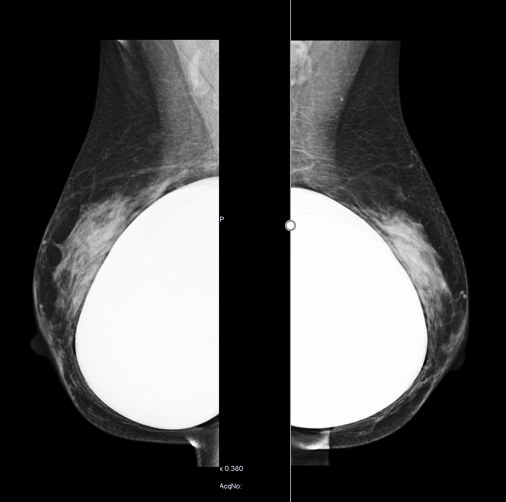

La mamografía actualmente es el método de imagen más utilizado tanto en el estudio de pacientes con síntomas mamarios como en pacientes asintomáticas, con el fin de diagnosticar el cáncer de mama en estadios iniciales. Es un método de imagen que conlleva radiación ionizante y necesita compresión de la mama para conseguir estudios de calidad. El estudio convencional consta de dos proyecciones de cada mama, una craneocaudal (CC) y otra oblicua medio lateral (OML). La realización de dos proyecciones en cada mama es fundamental para no pasar por alto lesiones visualizadas en una sola proyección, así como para realizar una correcta localización de estas.